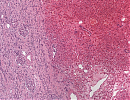

Mikroskopie

Ein scharf begrenzter epithelialen Tumor, aufgebaut aus soliden, überwiegend azinär und nestförmig, fokal auch trabekulär wachsenden Tumorzellverbänden. Die Tumorzellen monomorph mit runden mittelgroßen Zellkernen mit feinkörnigem Chromatin und einem breiten, stark eosinophilen Zytoplasmasaum. Die Tumorzellverbände eingebettet in ein zartes fibrovaskuläres Stroma mit dünnwandigen Blutgefäßen. Die tuschemarkierte Resektionsfläche tumorfrei.

Makroskopisch charakteristisch sind eine braune Schnittfläche und eine zentrale narbige Einziehung bei großen Tumoren. Histologisch sind die Zellen der Onkozytome rund bis oval, das Zytoplasma ist homogen, azidophil und feinkörnig. Die Kerne der renalen Onkozytomzellen sind regelmäßig und rund bis oval. Nur sehr selten können Mitosen auftreten. Ein Grading oder eine Subtypisierung von Onkozytomen wird nicht durchgeführt.

Abb. 359: Der Tumor (rechts) zeigt ein infiltratives und verdrängendes Wachstum gegenüber dem umgebenden Nierengewebe (links).

Abb. 360: Monomorphe Tumorzellen mit runden Zellkernen, deutlichen Kerngrößenschwankungen und breiten, stark eosinophilen Zytoplasmasaum.